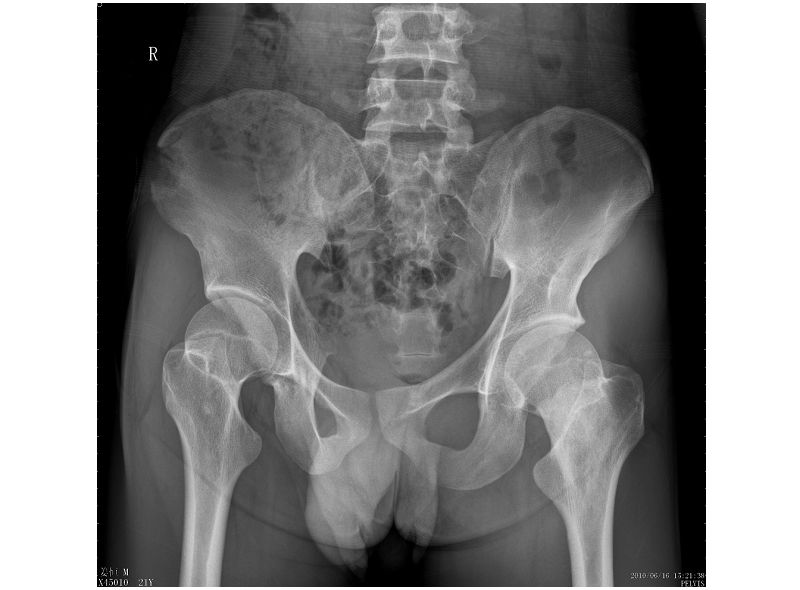

标题: CT27262:左股骨上段骨肿瘤 [打印本页]

标题: CT27262:左股骨上段骨肿瘤

男性,27岁,左髋部疼痛两三个月余,右侧髂骨因右侧股骨下端骨折,取骨植骨后改变